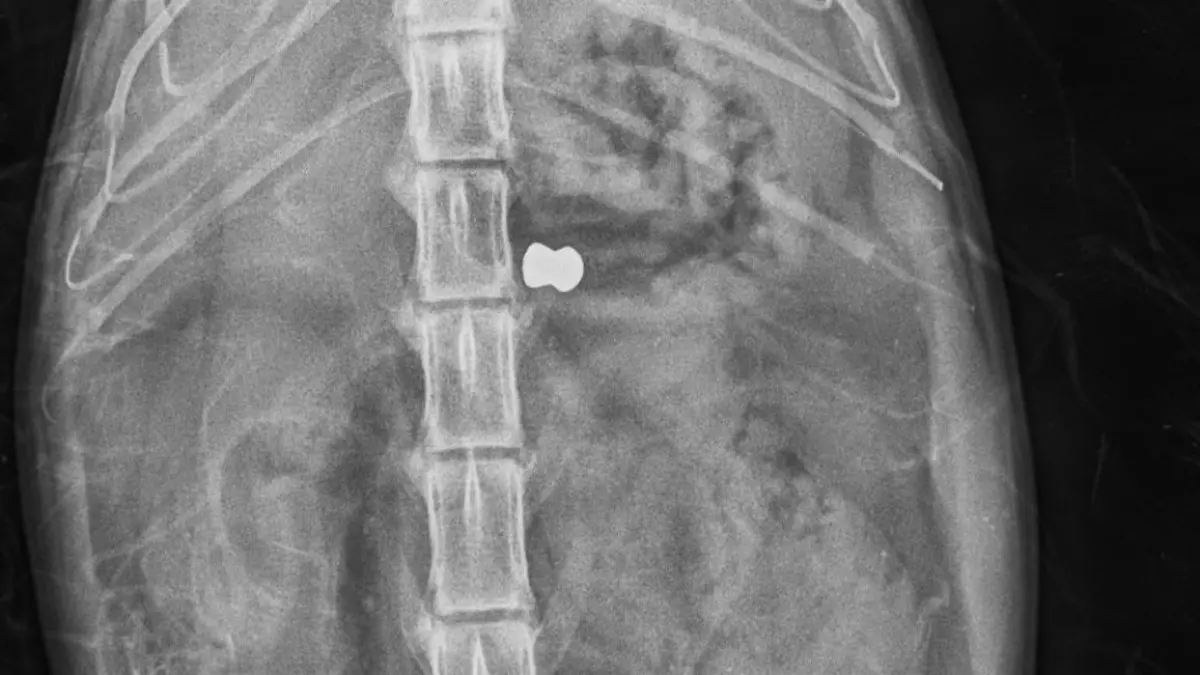

Der Grund: Das Tier hat fünf Kugeln in seinem Körper stecken – eine im Rücken, vier im Kopf. „Die Herzfrequenz war schon sehr, sehr verlangsamt. Dann habe ich gesehen, dass er die Geschosse in sich trägt, vor allem halt im Kopf. Das ist mit dem Leben so nicht mehr vereinbar gewesen. Der Kater war schon im Sterbeprozess.“ Um das Leid des Tieres nicht unnötig zu verlängern, haben sich Choucair und sein Team dazu entschieden, ihn einzuschläfern.

Der unkastrierte Kater war gerade einmal anderthalb Jahre alt und in einem guten Pflegezustand. Auch deshalb dachte Choucair zuerst, dass es sich um einen Autounfall handeln könnte. „Erst nach den Röntgenbildern habe ich das Ausmaß der Verletzungen abschätzen können. Also unseres Erachtens nach ist der Kater schlussendlich durch Menschenhand brutal hingerichtet worden. Anders kann man das nicht bezeichnen“, so der Tierarzt.

Zwar habe er schon häufiger gesehen, dass Diabolo-Geschosse - die Patronen aus einem Luftgewehr – Tiere verletzt hätten. Doch bei einem solchen Bild müsse man von einer furchtbaren Misshandlung sprechen. „Hier sind auch Tränen seitens der Mitarbeiter geflossen, weil das absolut nicht alltäglich ist. Das stimmt schon nachdenklich, dass es Mitmenschen auf dieser Welt gibt, die so etwas machen.“